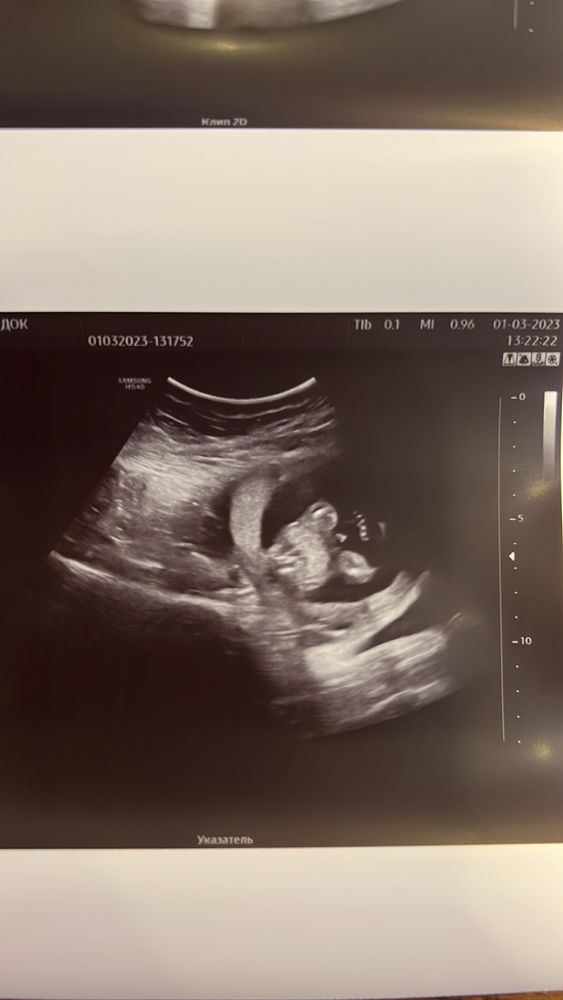

Узи на 16 недели ) пол ребенка

У меня с сыном такая пушка там была в 16н, я обалдела Думаю это девочка)

Как по мне очень даже без сомнений. Девочка тут. У них то же впирают половые губы и, да когда не знаешь ,то можно подумать, что машонка. Но нет . Когда я увидела мальчика тогда поняла что спутать такое нельзя)))

таню, я вот тоже видела мальчика на узи ) на экране в этот раз сразу поняла что дочка ) а фото когда дали , закрались сомнения ☺️

Девочка)

Девочка, у моей так же было)

Конечно девочка. У мальчиков «свисток» выпирает

Диана , я думаю, что тут можно не сомневаться, а начинать подбирать девчачие имя😉